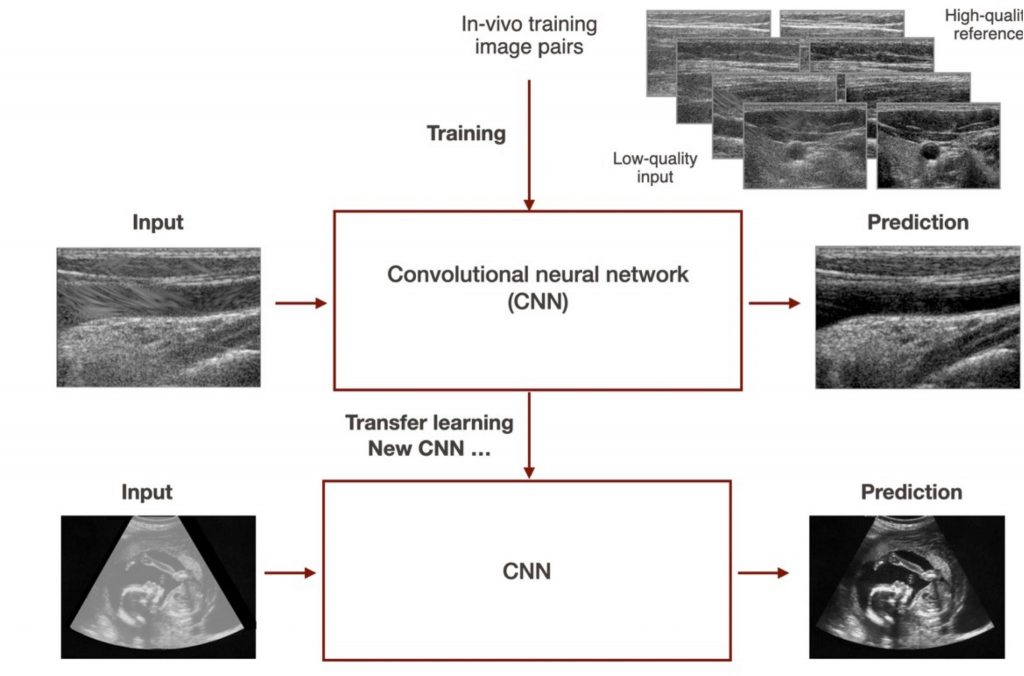

1. Domain adaptation for ultrasound image quality enhancement with deep learning

This project focuses on improving the image quality of ultrasound images using a deep-learning-based image reconstruction techniques. The goal is to adapt the current CNN to a different setting and equipment configuration, enabling imaging at greater depths and wider fields of view. Various approaches, including transfer learning and training from scratch, will be explored using a new dataset. The project will be applied to fetal and liver imaging and 3D tracked systems.

To acquire the dataset we will ask the student to use an ultrasound device after proper training, potentially receiving compensation for creating a large in vivo dataset.

1. Domain adaptation for ultrasound image quality enhancement with deep learning

This project focuses on improving the image quality of ultrasound images using a deep-learning-based image reconstruction techniques. The goal is to adapt the current CNN to a different setting and equipment configuration, enabling imaging at greater depths and wider fields of view. Various approaches, including transfer learning and training from scratch, will be explored using a new dataset. The project will be applied to fetal and liver imaging and 3D tracked systems.

To acquire the dataset we will ask the student to use an ultrasound device after proper training, potentially receiving compensation for creating a large in vivo dataset.